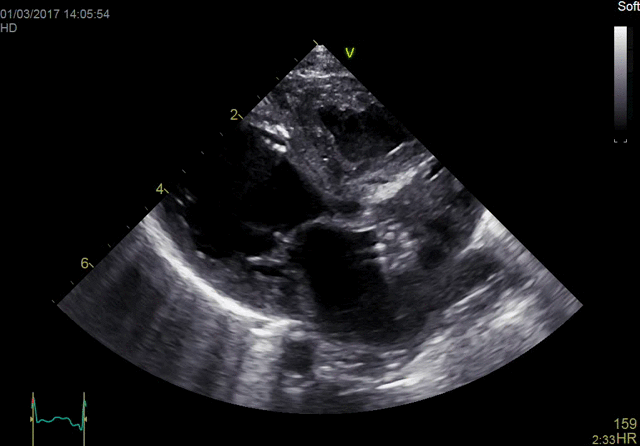

One patient, one probe The new one-probe adult 4D TTE solution on the Vivid™ E95 provides an excellent ergonomic workflow solution with uncompromised 2D, 4D, color and Doppler image quality performance at ultra-high volume rates - all with a single probe. This allows for complete and comprehensive diagnosis with one probe and avoids switching of probes, thereby reducing exam time and helping you move swiftly through your work with minimal muscular stress and strain on the operator.